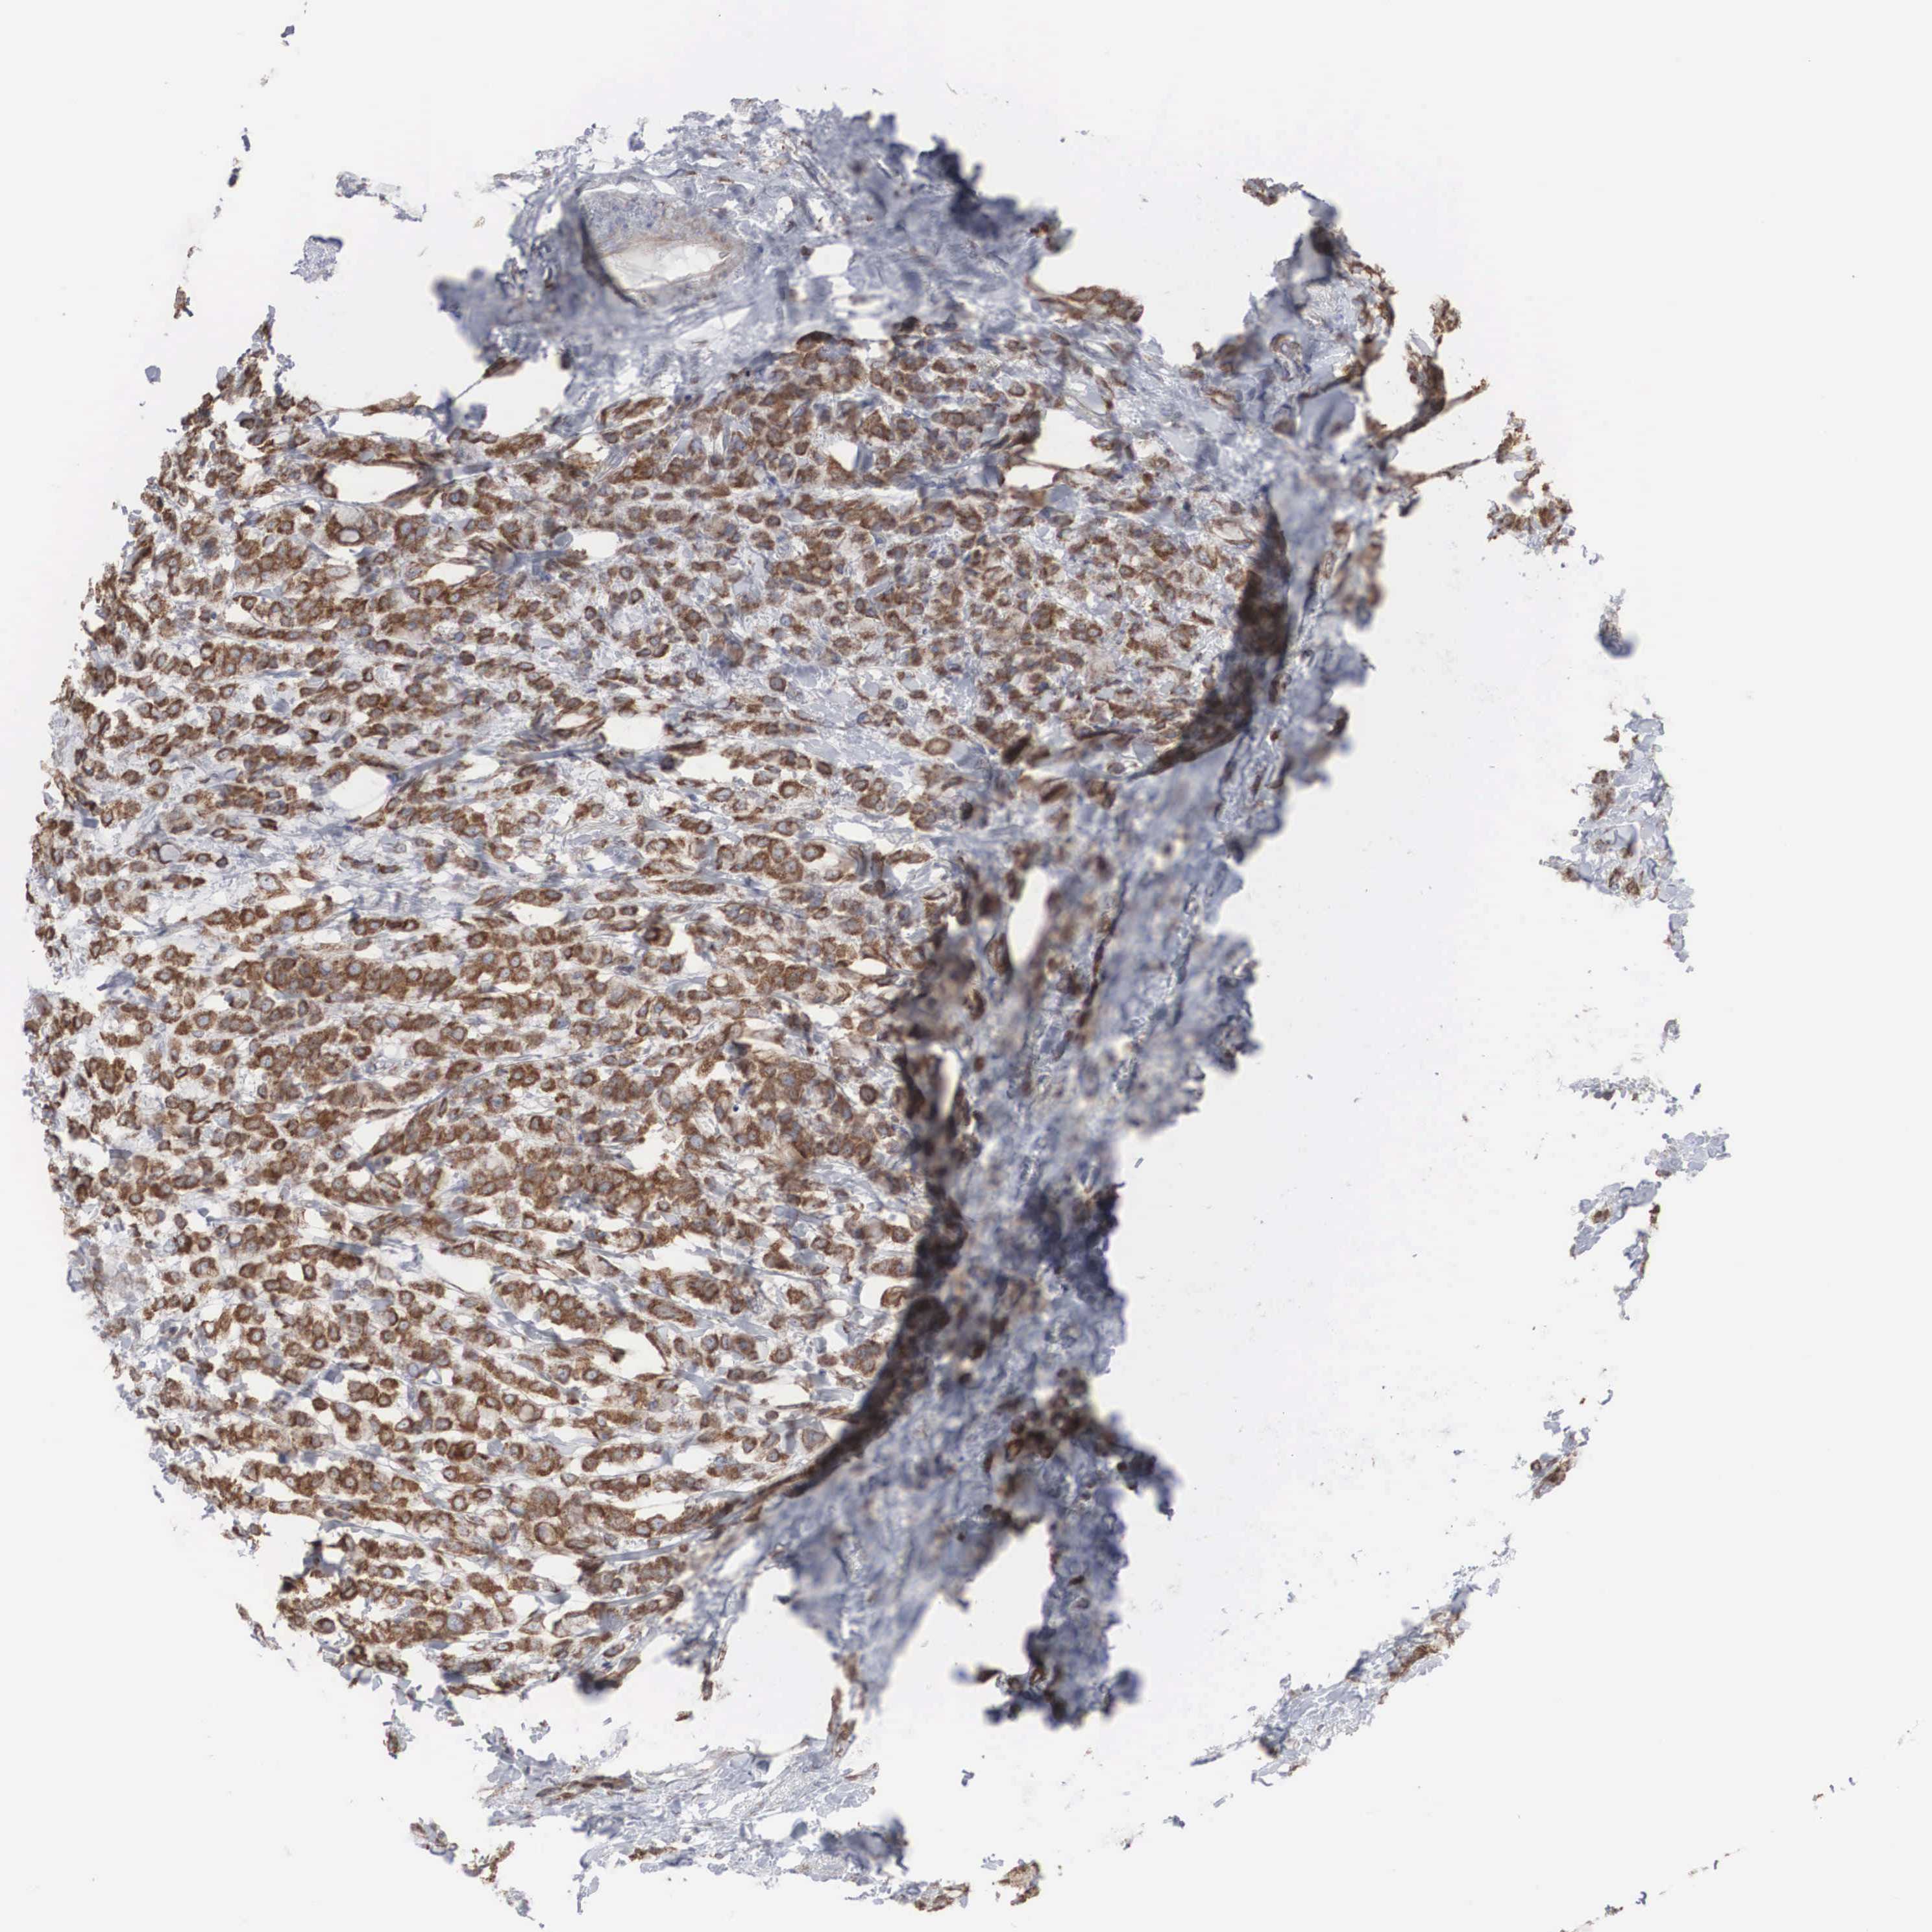

BREAST CANCER - Protein expressioni

A mouse-over function shows sample information and annotation data. Click on an image to view it in a full screen mode. Samples can be filtered based on level of antibody staining by selecting one or several of the following categories: high, medium, low and not detected. The assay and annotation is described here.

Antibody stainingi

Antibody staining in the annotated cell types in the current human tissue is reported as not detected, low, medium, or high, based on conventional immunohistochemistry profiling in selected tissues. This score is based on the combination of the staining intensity and fraction of stained cells.

Each image is clickable and will lead to virtual microscopy that enables deeper exploration of all samples and also displays staining intensity scores, fraction scores and subcellular localization as well as patient and tissue information for each sample.

Antibody HPA000387

Staining

High

Medium

Low

Not detected

Intensity

Strong

Moderate

Weak

Negative

Quantity

>75%

75%-25%

<25%

None

Location

Nuclear

Cytoplasmic/membranous

Cytoplasmic/membranous,nuclear

Duct carcinoma

Lobular carcinoma

Neoplasm, malignant, NOS